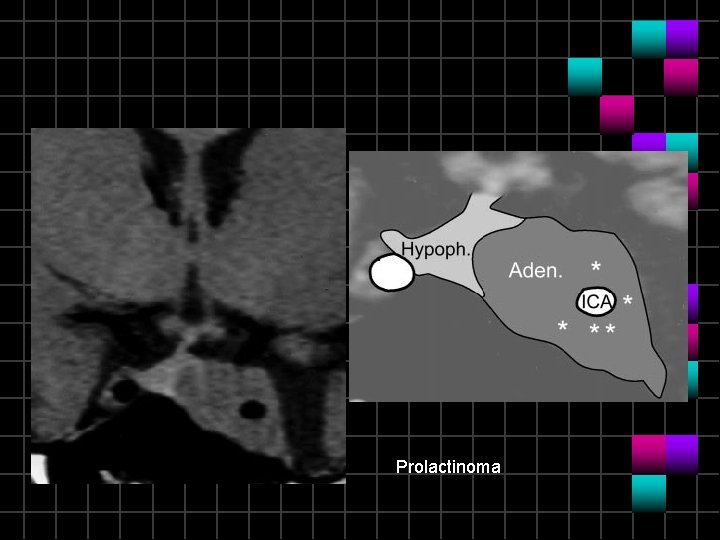

Prolactinoma

Prolactinoma Invasión de ACI de 25%